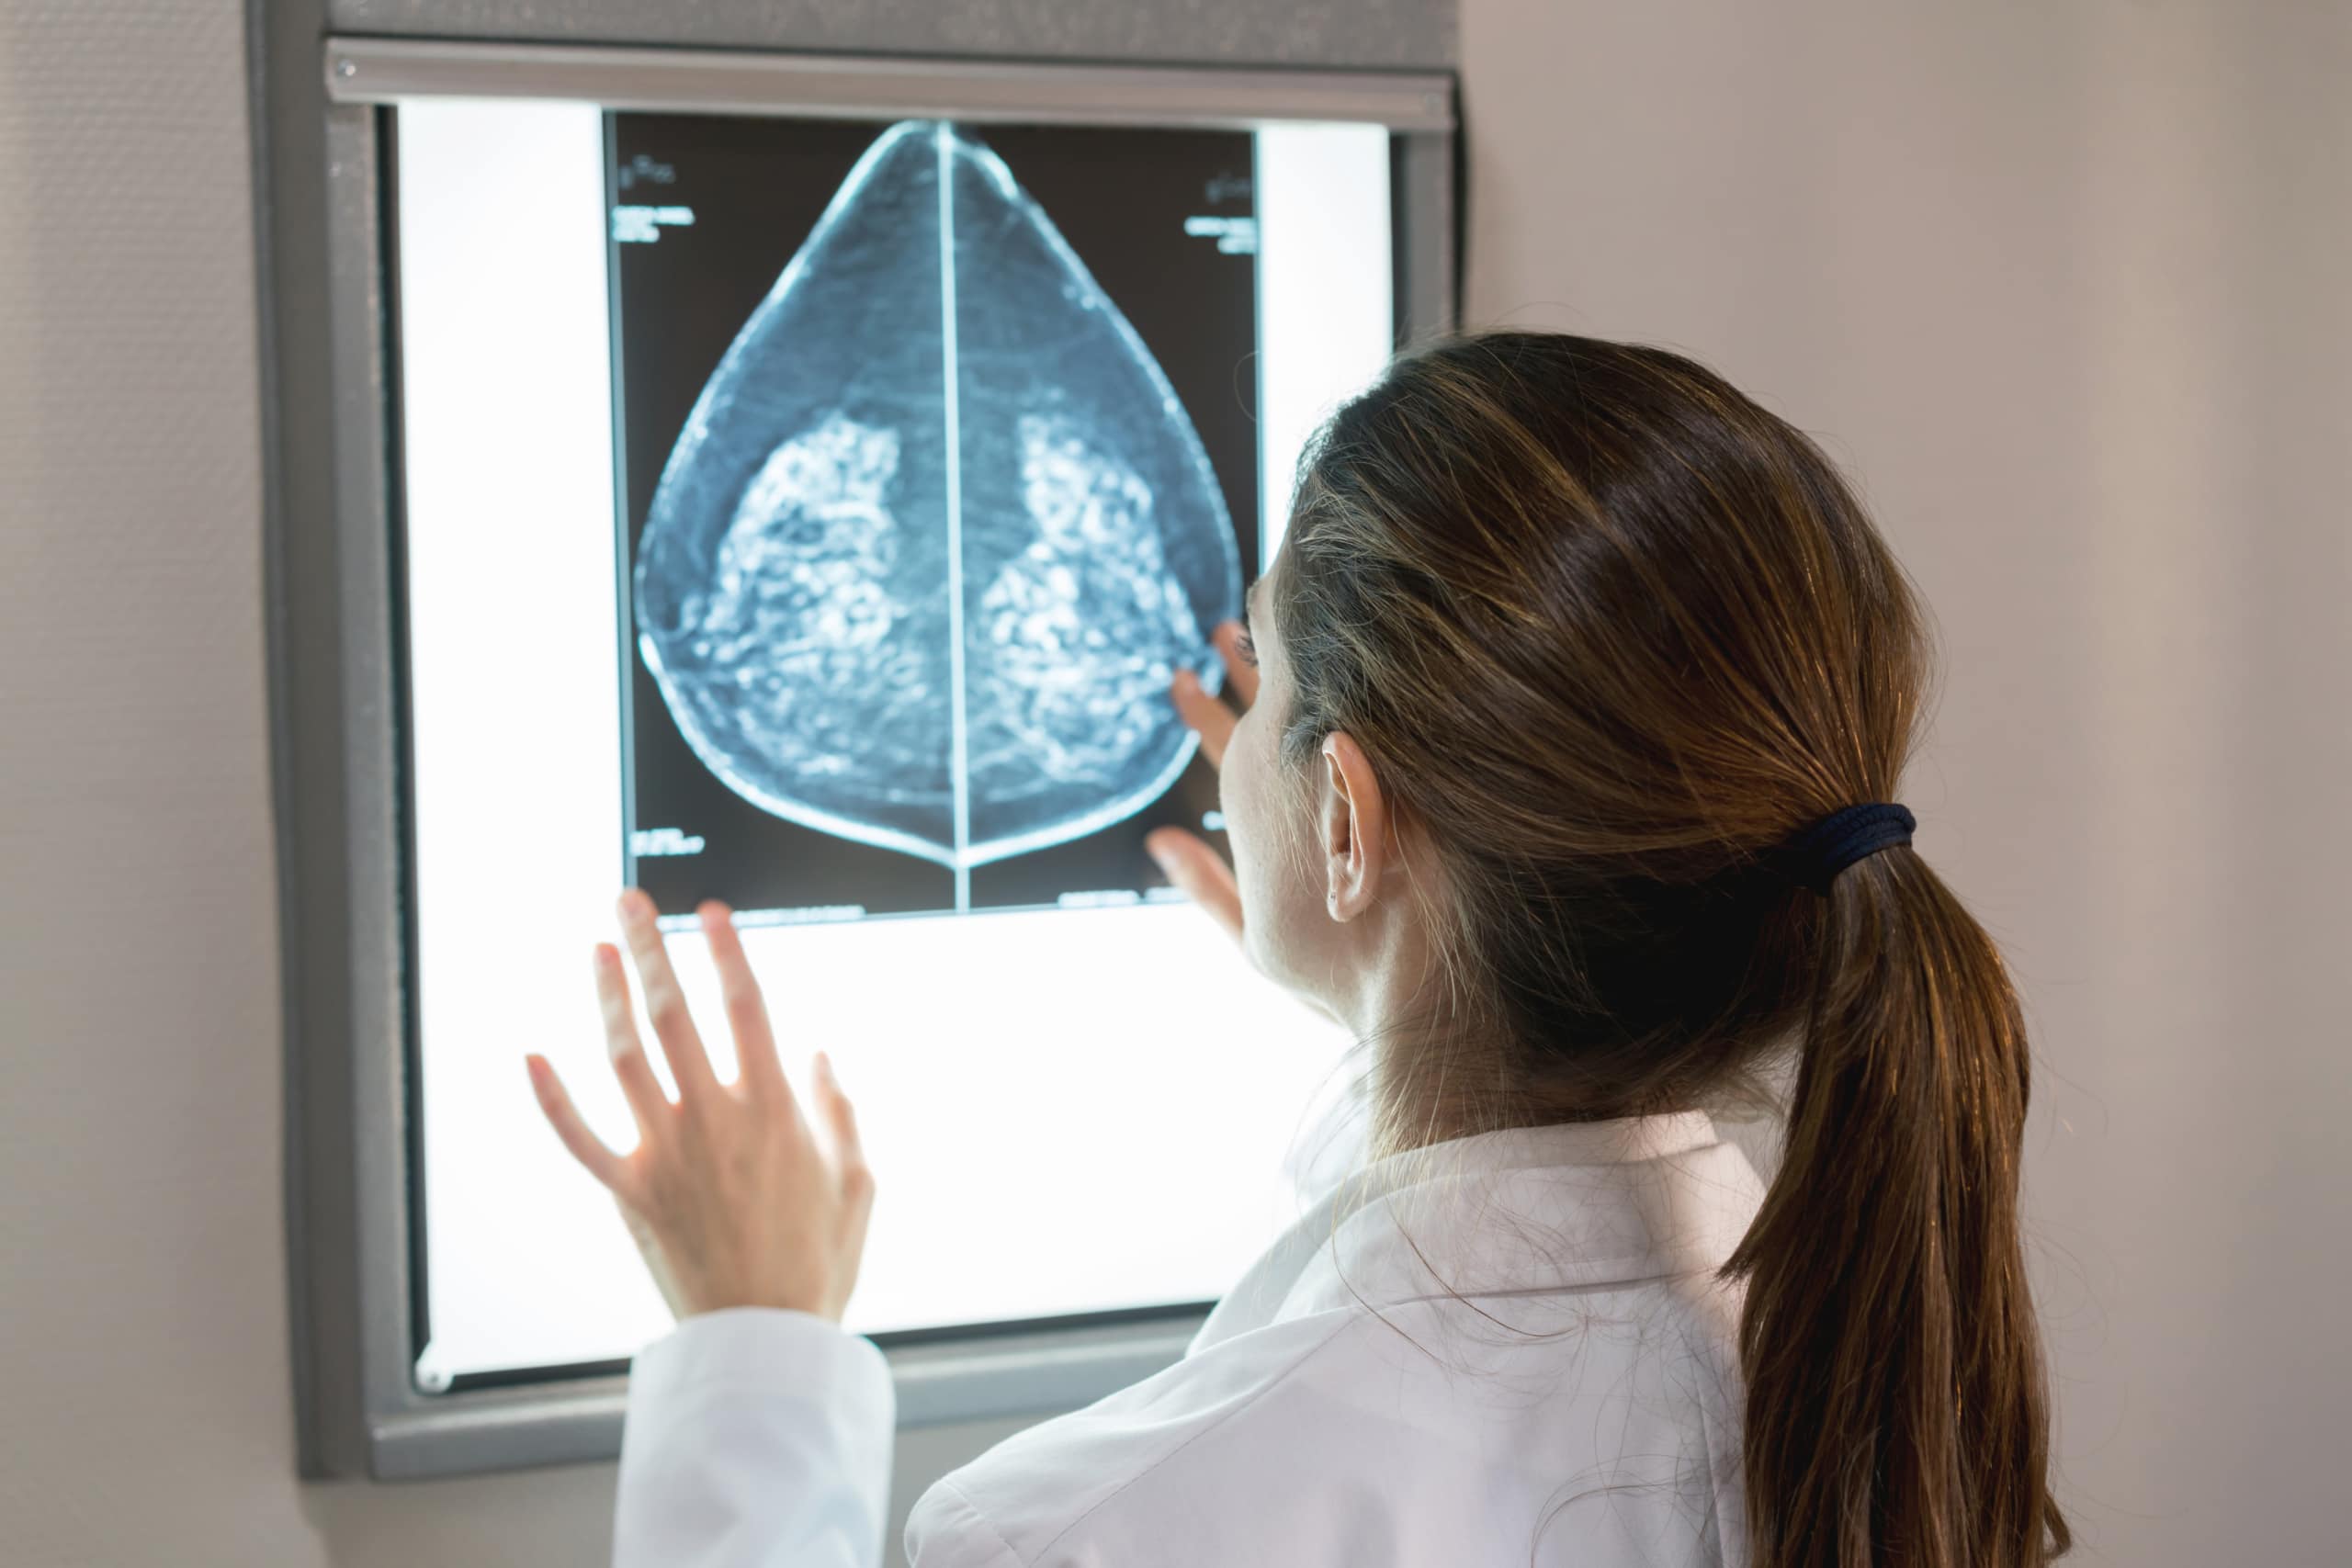

The term ‘triple negative’ is used to describe a type of breast cancer that does not have any of the three receptors commonly found on breast cancer cells. These receptors are:

Because of its triple negative status (Oestrogen Receptor negative, Progesterone Receptor negative and Human Epidermal Growth Factor Receptor 2 negative) this cancer type generally does not respond to receptor targeted treatments.

Depending on the stage of its diagnosis, Triple Negative Breast Cancer can be particularly aggressive, and more likely to recur than other subtypes of breast cancer.

Treatment for triple negative breast cancer usually involves surgery (lumpectomy or mastectomy), radiotherapy if a lumpectomy was performed, and chemotherapy. It generally responds well to chemotherapy.